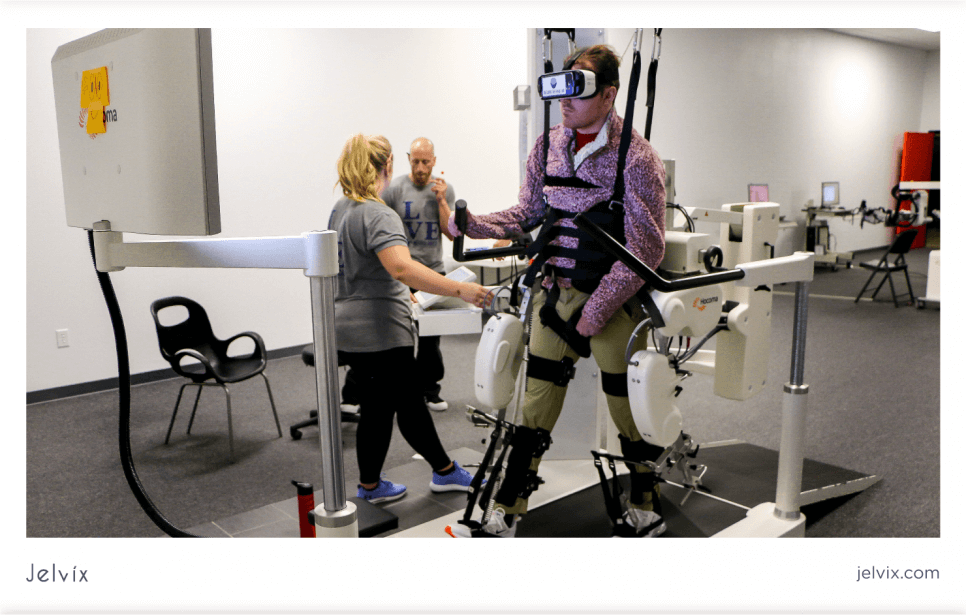

ARTICLE - Virtual Reality in Healthcare

By Vitaliy Ilyukha, Head of Technology | Jelvix | Acessed on April, 2022

Today virtual reality in healthcare is on a rapid rise, and many well-known companies are using it in a novel way to improve the health care system all around the world. The healthcare industry used virtual reality throughout its various sectors to provide high-quality care to patients and medical professionals alike. On top of that, virtual reality is being used in everything from surgical preparation to patient illness and therapy.

By Vitaliy Ilyukha, Head of Technology | Jelvix | Acessed on April, 2022

Today virtual reality in healthcare is on a rapid rise, and many well-known companies are using it in a novel way to improve the health care system all around the world. The healthcare industry used virtual reality throughout its various sectors to provide high-quality care to patients and medical professionals alike. On top of that, virtual reality is being used in everything from surgical preparation to patient illness and therapy.

Infographic - Virtual Reality in Healthcare

By Vitaliy Ilyukha, Head of Technology| Jelvix | Accessed on April, 222

Full article by Vitaliy Ilyukha | Jelvix | Accessed on April, 2022

By Vitaliy Ilyukha, Head of Technology| Jelvix | Accessed on April, 222

Full article by Vitaliy Ilyukha | Jelvix | Accessed on April, 2022